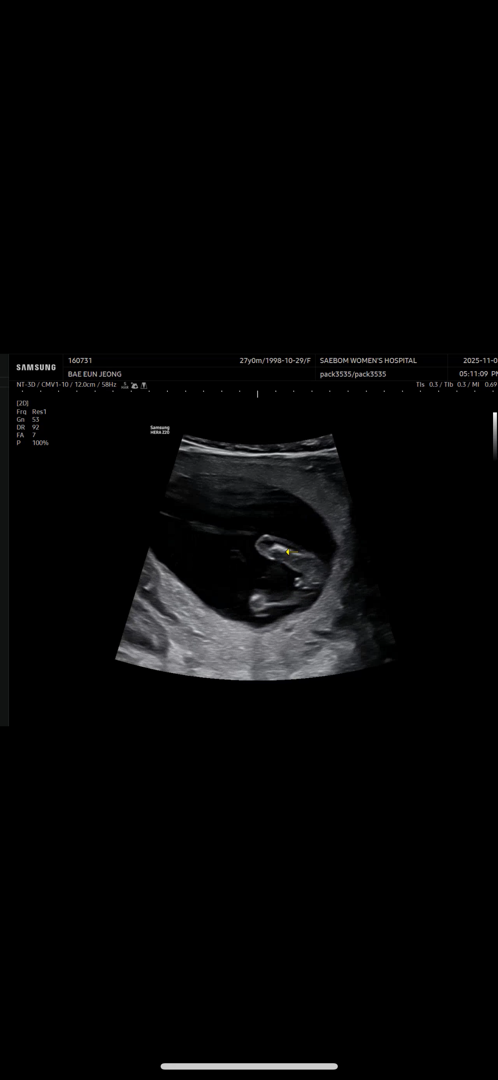

각도법 봐주세요!!

병원에서는 딸인거같다고 하는데 엉덩이 뒤쪽 살짝 남자아이 같이 튀어나온거같아서 질문드려요...!

이사진이랑 같이 비교해서 각도법 봐주세요!!